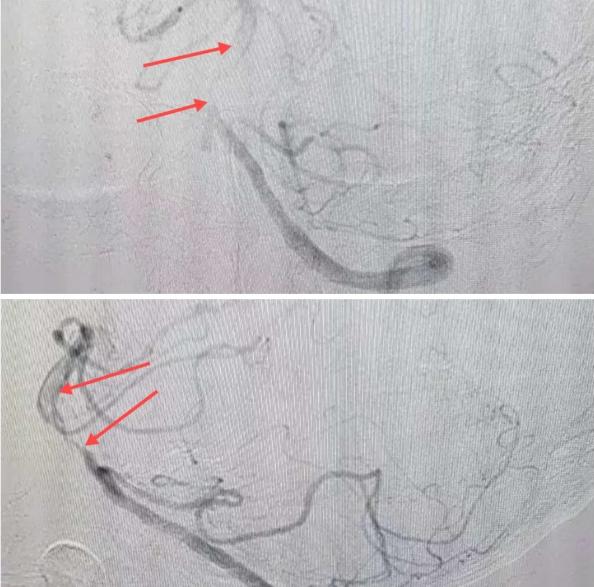

在經(jīng)造影后,主刀醫(yī)生腦一科副主任楊慶堂發(fā)現(xiàn)患者基底動(dòng)脈下段重度狹窄且狹窄段以遠(yuǎn)有大負(fù)荷血栓,其狹窄處考慮為動(dòng)脈夾層,手術(shù)難度及風(fēng)險(xiǎn)較大。楊慶堂副主任在彭壯副主任醫(yī)師的協(xié)助下運(yùn)用spaceman(太空人)技術(shù),中間導(dǎo)管抵近血栓抽吸配合支架拉栓,成功開通血管。再次造影可見基底動(dòng)脈管腔明顯增寬,遠(yuǎn)端血管顯影良好,且等待20分鐘后造影仍顯示血流通暢。楊慶堂副主任考慮到本次手術(shù)時(shí)間不宜過長(zhǎng),現(xiàn)患者基底動(dòng)脈及分支前向血流維持良好,給予其抗栓藥物應(yīng)用后結(jié)束手術(shù),并建議患者3個(gè)月后復(fù)查造影,明確其基底動(dòng)脈夾層情況。

造影可見血管夾層和大量血栓形成

取栓后血管管腔增寬,前向血流良好